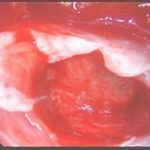

手術前1

摘出 前